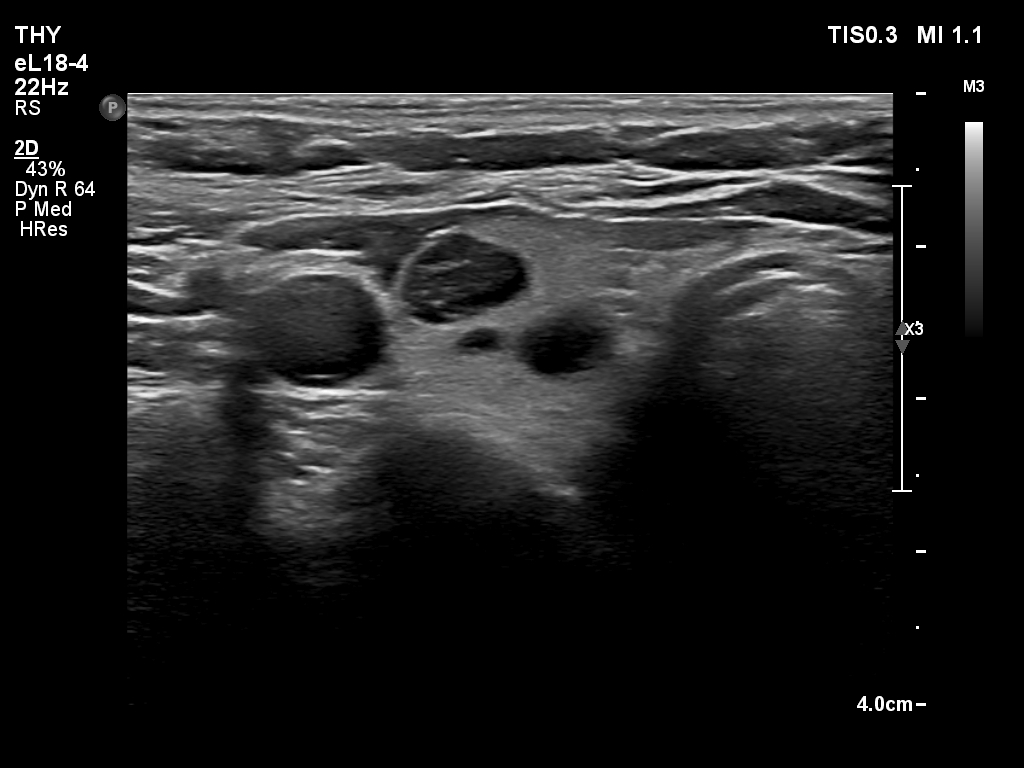

Ultrasonography. The thyroid was echonormal and had multiple nodules. There were cystic areas, an almost completely cystic nodule, and a dominantly solid nodule in the right lobe. The left lobe had three lesions. The upper solid lesion was the one we treated 16 years ago. The middle lesion was a dominantly solid while the lower one seemed to be a pure cyst. The dimensions of the nodule which has been treated with sclerotherapy were 10x11x13 mm (width, depth and length, respectively). There was a large cystic nodule in the upper pole of the left lobe. The lesion showed relatively large hyperechogenic granules. There were multiple enlarged lymph nodes lateral to the left lobe, two of largest were cystic.